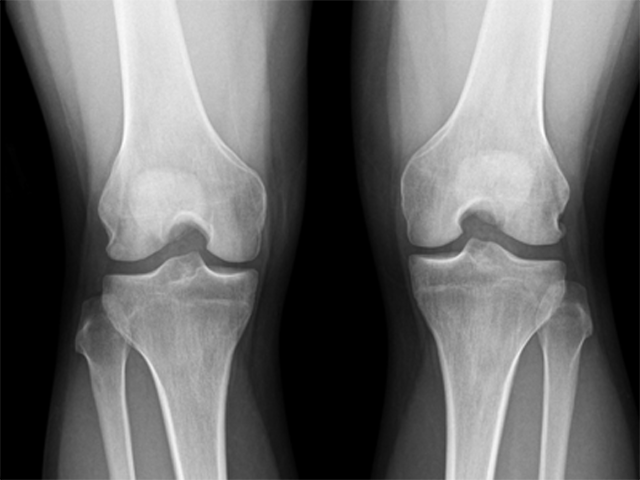

관절염은 무릎 관절을 보호하고 있는 연골의 손상이나 노화로 인한 퇴행성 변화로 인해 연골이 닳아 없어지는 질환입니다.

관절염은 나이가 들며 누구에게나 발생할 수 있는 질환으로, 특히 무릎의 경우 몸의 하중의 많은 부분을 부담하고 있는 부위로 퇴행성 관절염이 가장 흔하게 발생되는 부위입니다.